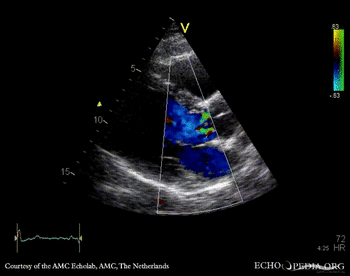

E00418.gif E00419.gif

PLAX: Color Doppler, moderate aortic regurgitation PSAX